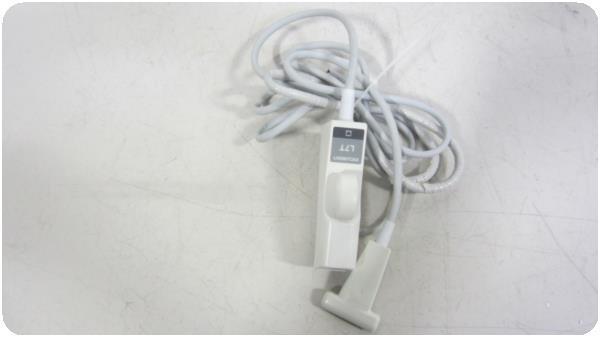

Acuson Linear Ultrasound Probe 7L3 08267217

Sale price$ 3,837.58